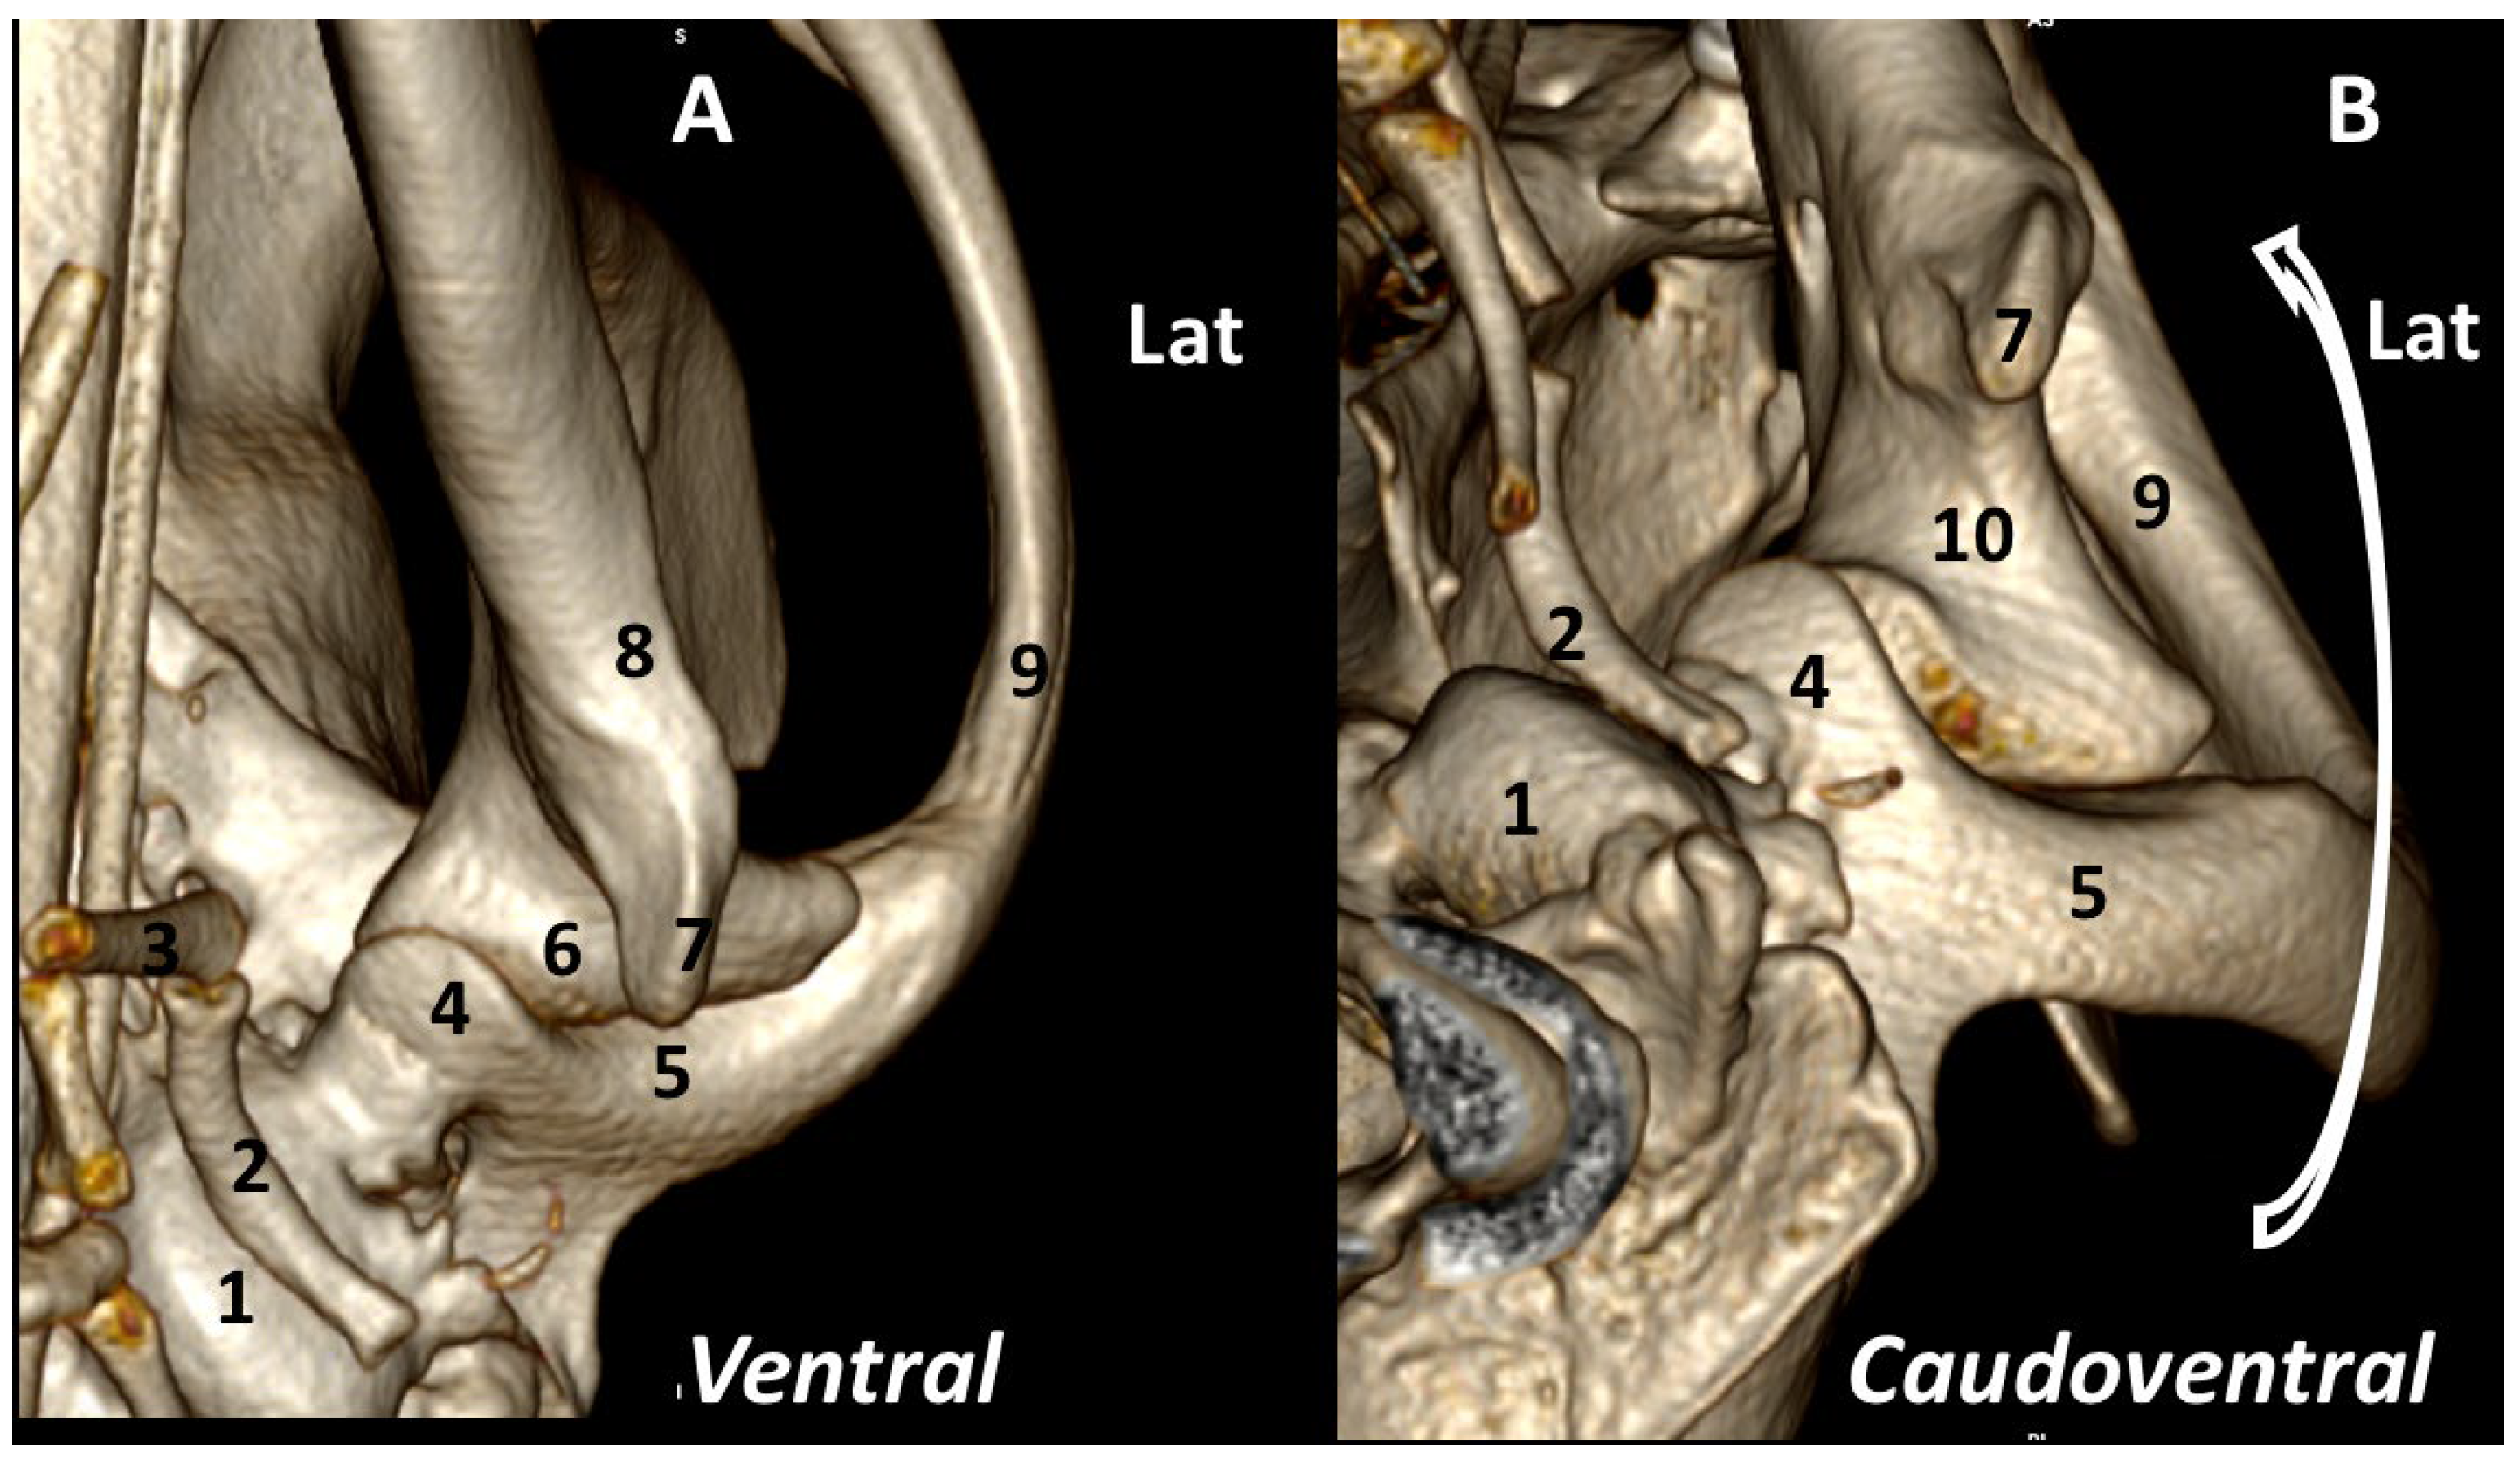

3.1. A Detailed Description of the Bone Anatomy of TMJ Using 3DVR Images